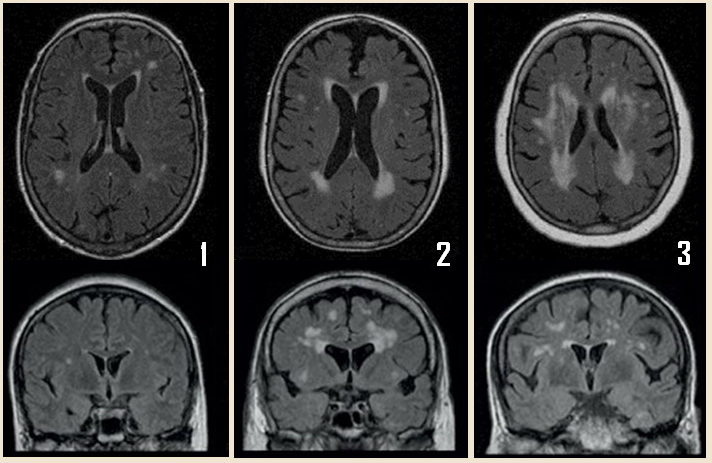

Fazekas grades. Fazekas степени мрт. Фазекас 2 мрт. Шкала Фазекас мрт. Лейкоареоз 3 степени по Fazekas.

Fazekas grades. Fazekas степени мрт. Фазекас 2 мрт. Шкала Фазекас мрт. Лейкоареоз 3 степени по Fazekas.

Fazekas grades. Классификация Фазекас. Fazekas мрт. Лейкоареоз степени по Fazekas. Фазекас классификация мрт.

Fazekas grades. Классификация Фазекас. Fazekas мрт. Лейкоареоз степени по Fazekas. Фазекас классификация мрт.

Fazekas grades. Фазекас классификация мрт. Лейкоареоз Fazekas 1 что это. Fazekas степени мрт. Лейкоареоз степени по Fazekas.

Fazekas grades. Фазекас классификация мрт. Лейкоареоз Fazekas 1 что это. Fazekas степени мрт. Лейкоареоз степени по Fazekas.

Fazekas grades. Фазекас 2. Fazekas 0. Фазекас 3.

Fazekas grades. Фазекас 2. Fazekas 0. Фазекас 3.